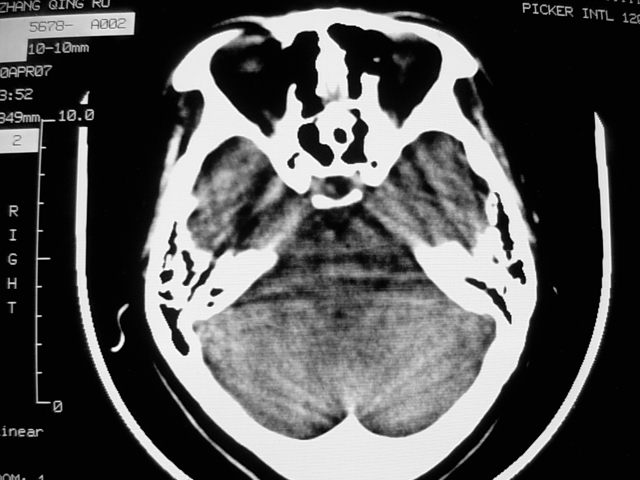

f39y,头疼、眩晕。患者拒绝强化。

左额叶见一巨大椭圆形略低、低密度混杂密度肿块,边界清楚,似与侧脑室额角相通,明显占位效应,左侧侧脑室受压变形,右侧侧脑室扩大,中线结构向右明显弧形移位。鞍上池闭塞。

考虑:1、左额叶良性占位性病变,以皮样囊肿可能性大,伴镰下疝。

2、建议增强扫描或mri进一步检查。

感觉病灶位于侧脑室前角内,而体部受压,病灶形态同前角一致,右侧脑室前角变形并不太严重,病灶呈混杂密度,考虑皮样囊肿或室管膜瘤可能性大一些。